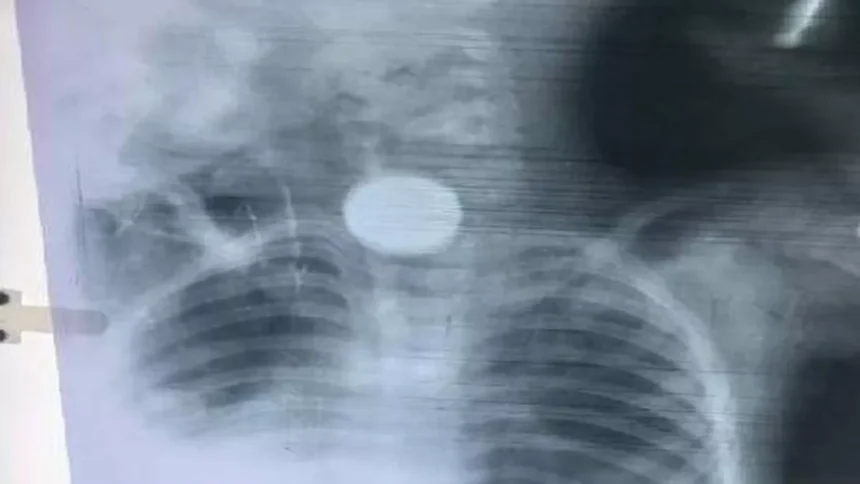

झारखंडः झारखंड के दुमका के गोपीकांदर प्रखंड के रांगा मिशन गांव में चार साल के राम मड़ैया के साथ एक दर्दनाक हादसा हुआ। मासूम ने खेल-खेल में एक सिक्का निगल लिया, जो उसके गले में फंस गया। उल्टियां शुरू होने पर परिजन उसे तुरंत सामुदायिक स्वास्थ्य केंद्र ले गए, लेकिन वहां से मेडिकल कॉलेज अस्पताल रेफर कर दिया गया।

मंगलवार को नाक, कान, गला विशेषज्ञ डॉ. आलोक कुमार ने सिक्का निकालने की कोशिश की, मगर अस्पताल में जरूरी यंत्र (ओसोफिलोस्कोप) न होने के कारण वे नाकाम रहे। मजबूरी में बच्चे को एम्स या रिम्स रेफर करना पड़ा। यह घटना दुमका मेडिकल कॉलेज की बदहाल स्वास्थ्य सुविधाओं की पोल खोलती है। हर सुविधा होने का दावा करने वाला यह अस्पताल एक छोटे से यंत्र के अभाव में बच्चे का इलाज नहीं कर सका।

डॉ. आलोक ने बताया कि सिक्का गले में काफी नीचे फंस गया था। ओसोफिलोस्कोप के बिना सिक्के का सटीक स्थान पता करना और उसे निकालना असंभव था। यंत्र की कमी के कारण मरीज को रेफर करना पड़ा। दो साल पहले एक एसआर (सीनियर रेजिडेंट) ने अपने निजी ओसोफिलोस्कोप से मरीजों का इलाज किया था।